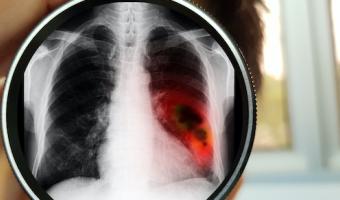

Unterstützung für Ihre Lungengesundheit Auf Mehr Luft erwarten Sie spannende, von Expert:innen aufbereitete Informationen und aktuelle Beiträge, die Ihre Lungengesundheit nachhaltig verbessern. Bild Bild was ist Asthma Bild was ist COPD Bild was ist Alpha-1 Bild Was ist Cystische Fibrose Bild Die Lunge - ein lebenswichtiges Organ - Etwa 300 Millionen stark durchblutete Lungenbläschen sorgen für den lebensnotwendigen Austausch zwischen Sauerstoff und Kohlendioxid. Funktionen der Lunge Wissenswertes für Sie Allgemein COPD Jederzeit richtig abhusten Entspannung Freizeit Mit Asthma oder COPD in die Sauna? Wohnen Allergisches Asthma und Schimmel Freizeit „Weltknuddeltag“: Der Einsamkeit entgegentreten Allgemein COPD Diagnose COPD: wie gehe ich damit um? Asthma COPD Die richtige Inhalationstechnik Allgemein Freizeit Entspannung gegen Stress, Ärger und Schmerzen Asthma COPD Durchatmen im Beruf mit Asthma oder COPD Mehr Artikel Expertentipps Unsere spannenden Umfrageergebnisse werden von Top-Expert:innen diskutiert und besprochen. ZU DEN TIPPS Bild Richtig inhalieren Ein Inhalator kann bei einem Asthmaanfall Leben retten - allerdings nur, wenn er richtig benutzt wird. VIDEO Bild Asthma Notfall Richtiges Verhalten bei einem Asthma Notfall beugt Ängste vor und ist von zentraler Bedeutung. Notfallplan Bild Genie hilft Hier finden Sie weiterführende Links zu Informationen Ihrer wichtigsten Fragestellungen. Zum Genie Bild ZurückWeiter Newsletter Jetzt zum Newsletter anmelden und laufend informiert bleiben! Vorname Nachname E-Mail Zustimmung zur Verarbeitung personenbezogener Daten Ich stimme zu, dass meine personenbezogenen Daten - wie in der Datenschutz-Richtlinie beschrieben - zur Zusendung und Analyse der E-Mailings verarbeitet werden. Diese Zustimmung kann ich jederzeit mit Wirkung für die Zukunft widerrufen. *Pflichtfeld Bitte dieses Feld leer lassen Bild Finde uns jetzt auch auf Social Media! Abonniere uns auf Facebook, Instagram oder LinkedIn für aktuelle News und Infos. Mehr-Luft.at @mehrluft.at Mehr-Luft.at